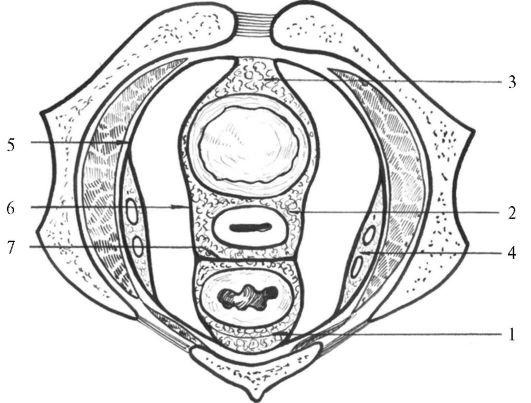

Анатомия малого таза: детальные схемы и изображения